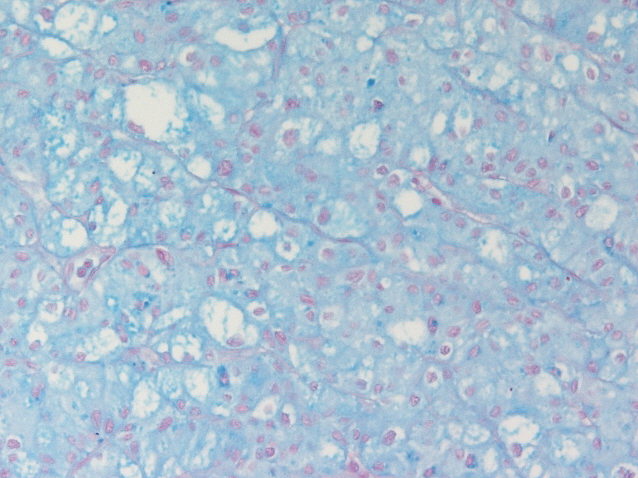

Renal tumor grading

Case ID: 882